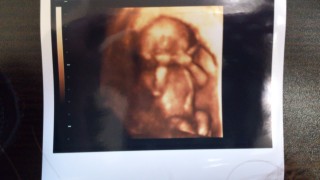

手足も長いし、指もちャんと5本見えるね♪と先生から言われました!この日は体育座りをしていてなかなか性別を教えてくれませんでした-。可愛すぎてもぉパパもベタ惚れです★

性別も男の子と言われましたヽ(^o^)丿